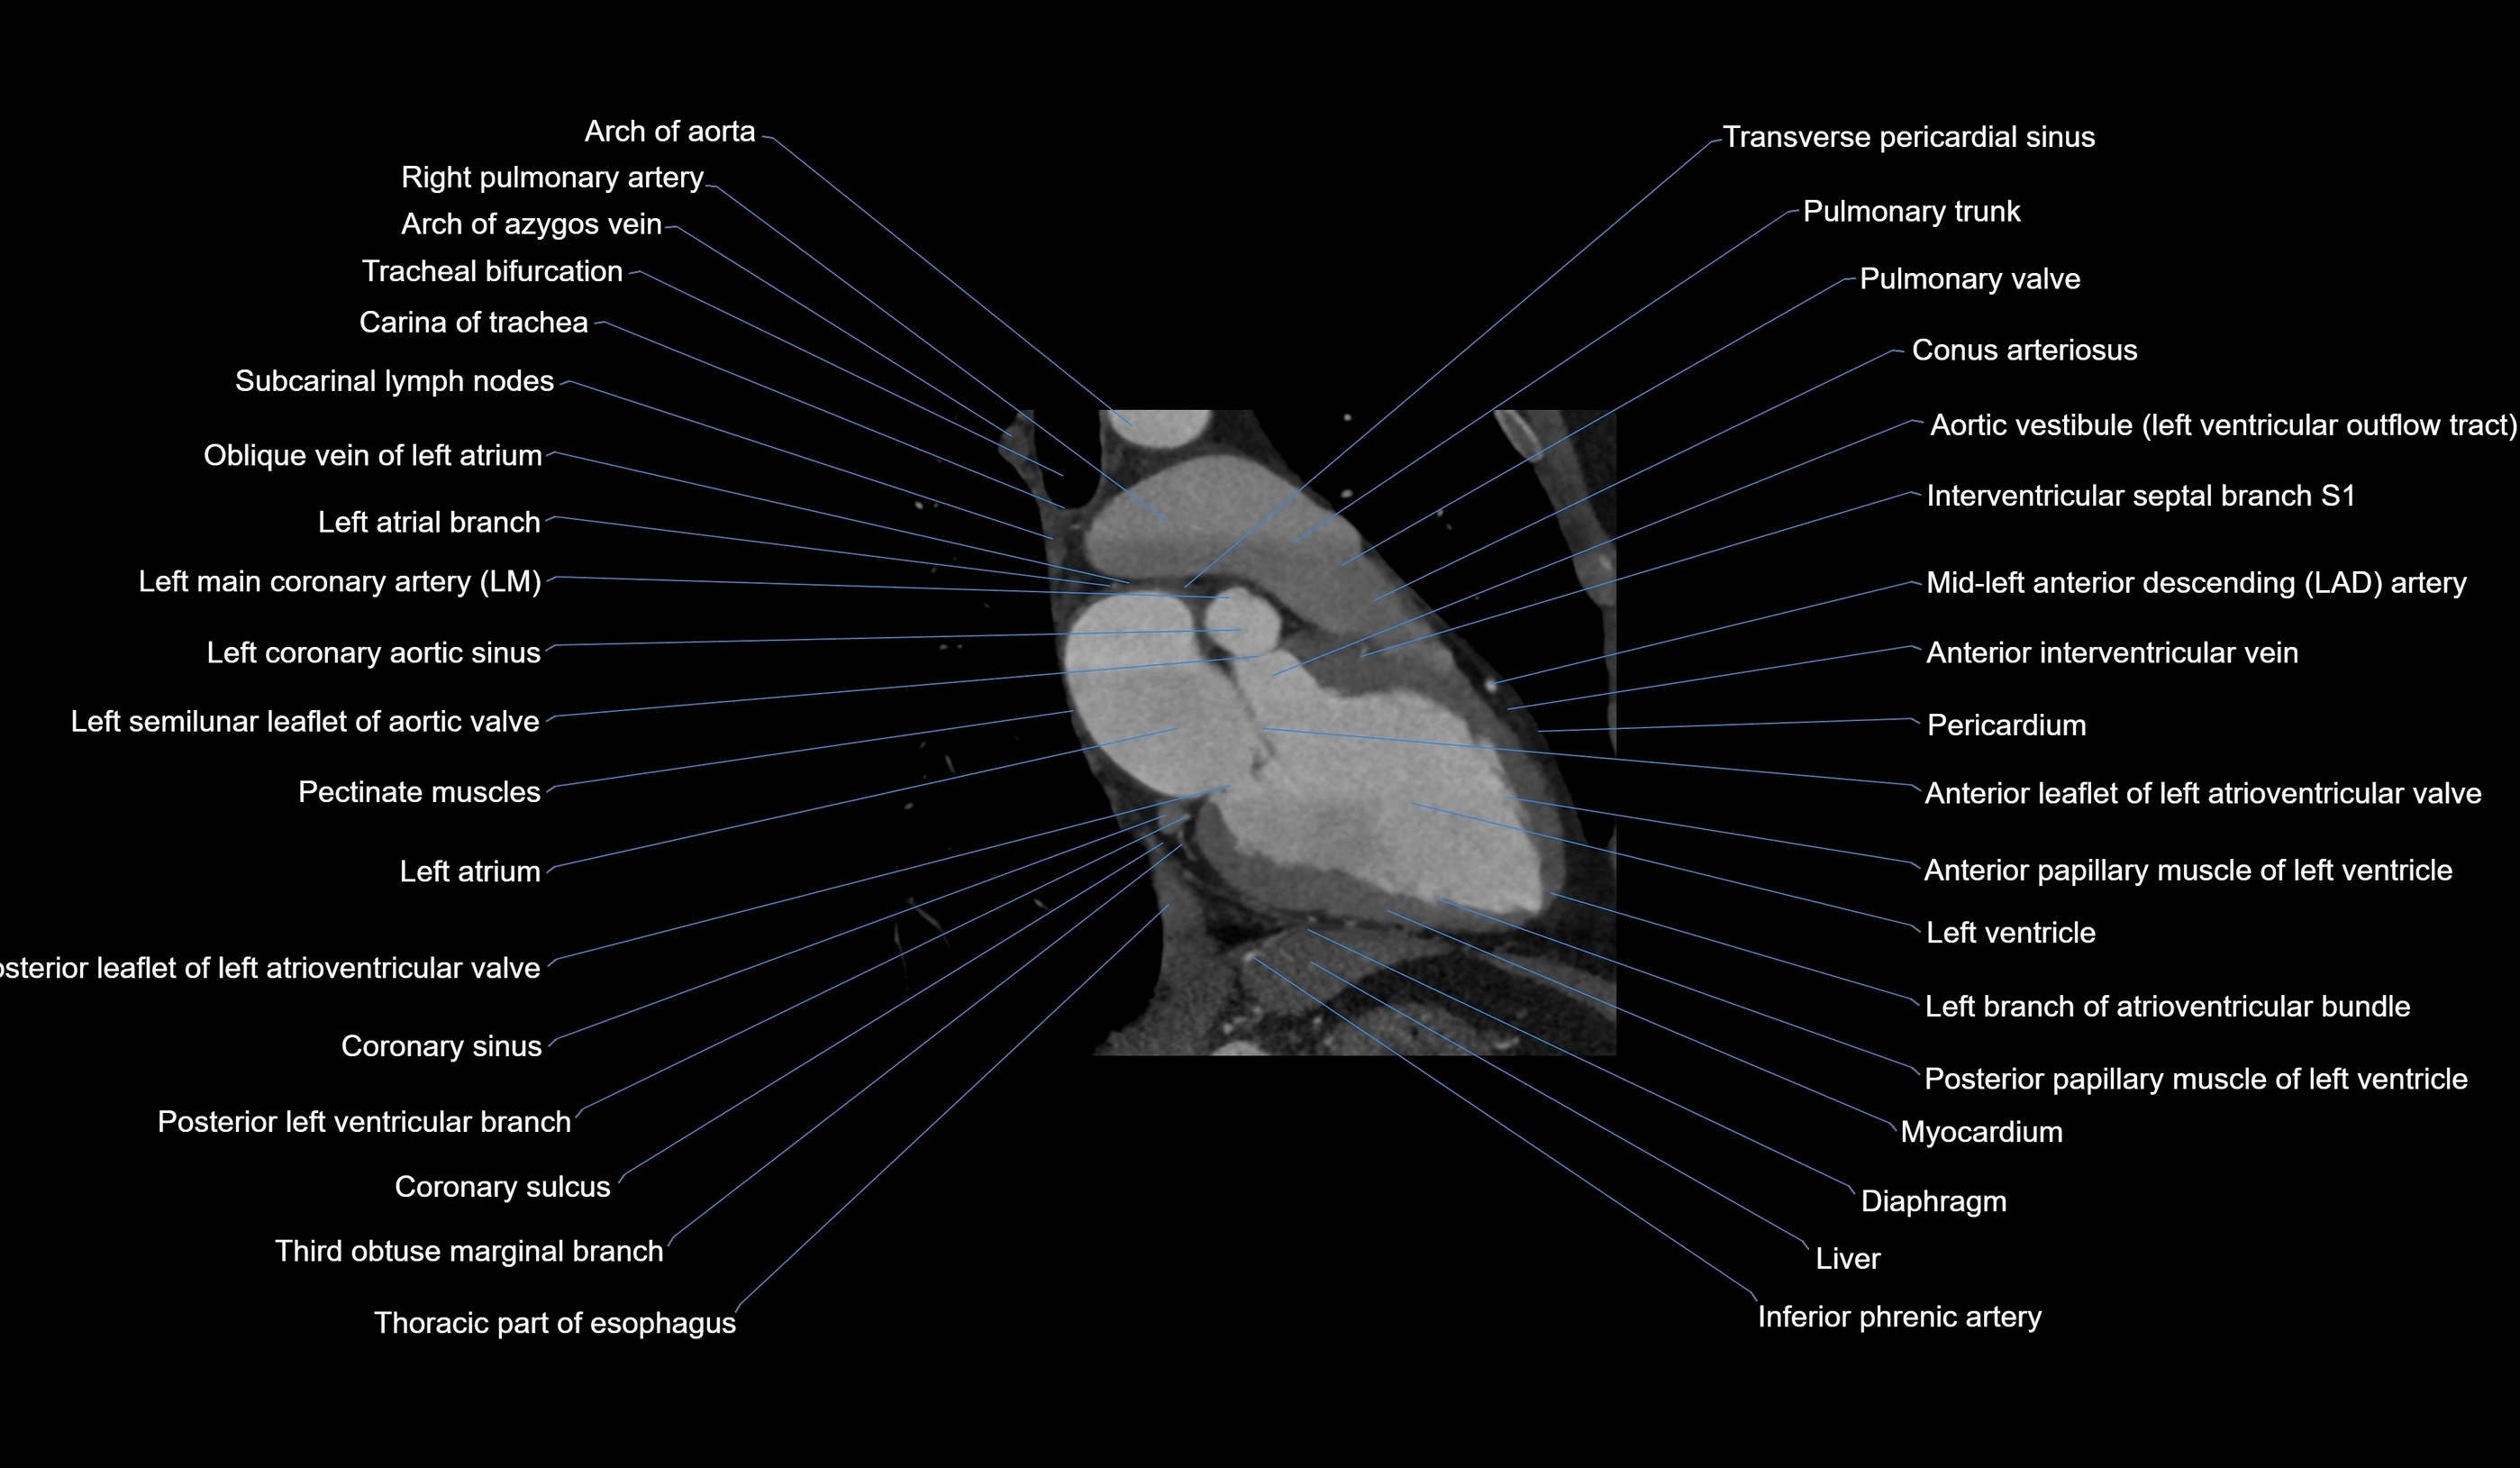

CT images